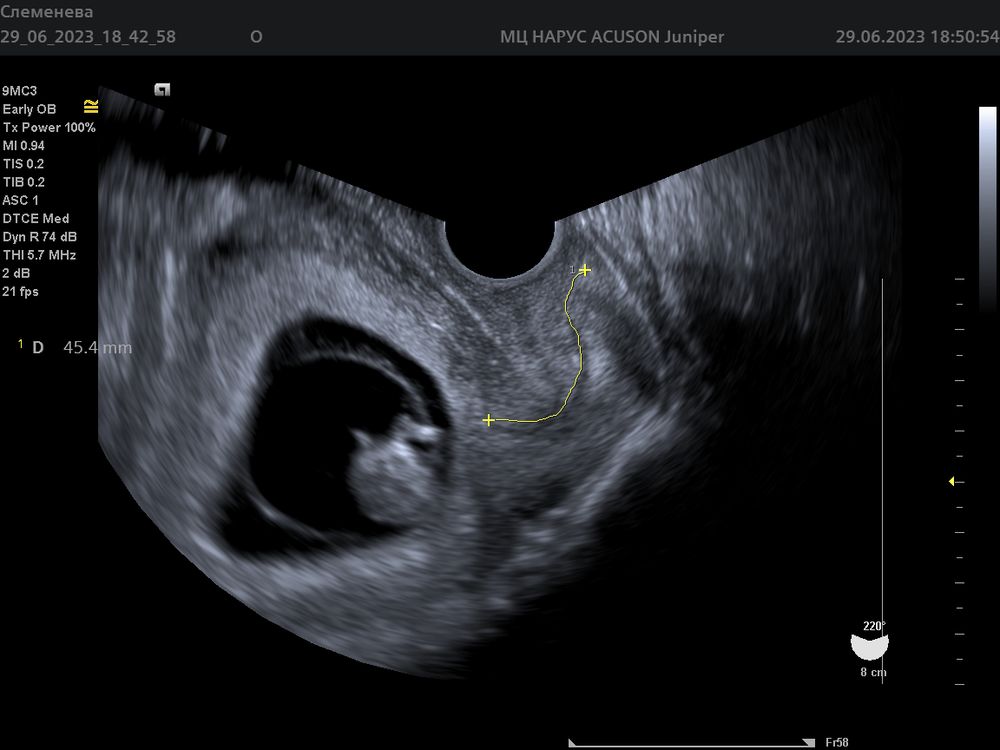

Ксения Слеменева в Благополучная беременность 2 года Что за линия? 10 недель УЗИ, КТГ, доплер Девочки, кто-то знает что это за линия желтым отмечена? Увидела только дома, врач ничего не говорил Посмотрите еще 20 записей на эту тему Отменить Ответить Маша Это шейка👍🏼 01.07.2023 Ответить Катрин Длина шейки матки) отличная для вашего срока 30.06.2023 Ответить Ксения Слеменева Катрин , спасибо большое за ответ🙏🏻 01.07.2023 Ответить Эмма Это шейка матки, длина 45,4 мм 👌 30.06.2023 Ответить Ксения Слеменева Эмма, спасибо за ответ🌸 01.07.2023 Ответить Наша маленькая креветочка🥰 Нарушение плодово-плацентарного кровотока 1Б степени на 30 неделе. Чаты Беременных Выберите чат: Январята-2026 Февралята-2026 Мартята-2026 Апрелята-2026 Майчата-2026 Июнята-2026 Июлята-2026 Августята-2026